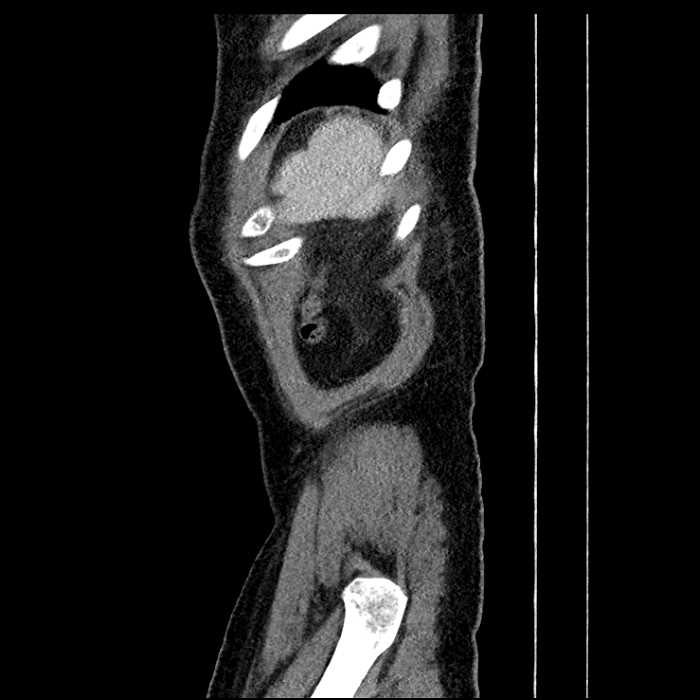

• Mild mural thickening of a segment of the sigmoid colon with adjacent fat stranding and a 1.5 cm fluid and gas collection along the tip of an inflamed diverticulum

• Loss of the normal fat plane between this collection and adjacent loops of small bowel, which demonstrate mural thickening

• No bowel obstruction

Acute sigmoid diverticulitis complicated by a small contained perforation and a large abscess in the right hepatic lobe. Additional small subcapsular abscesses along the anterior margin of the left hepatic lobe.

Additionally, loss of the normal fat plane between the peridiverticular collection and adjacent thickened loops of small bowel raises the potential for an enterocolonic fistula.

Hepatic abscess showing the double target sign with low density internally surrounded by a thin inner enhancing rim (red arrow) and ill-defined outer low density rim (yellow arrow). Blue arrow indicates an internal septation. Red arrows: additional smaller subcapsular abscesses. Red arrow: focal contained perforation associated with diverticulitis.